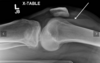

Describe the Insall-Salvati ratio

- Used to diagnose abnormal high/low riding patella - Lateral knee x-ray with knee 30 deg. Flexed Patellar tendon length / patellar length Normal ratio 0.8 - 1.2 (0.74 - 1.5 in other sources) Patella Baja = < 0.8 Patella Alta = >1.2